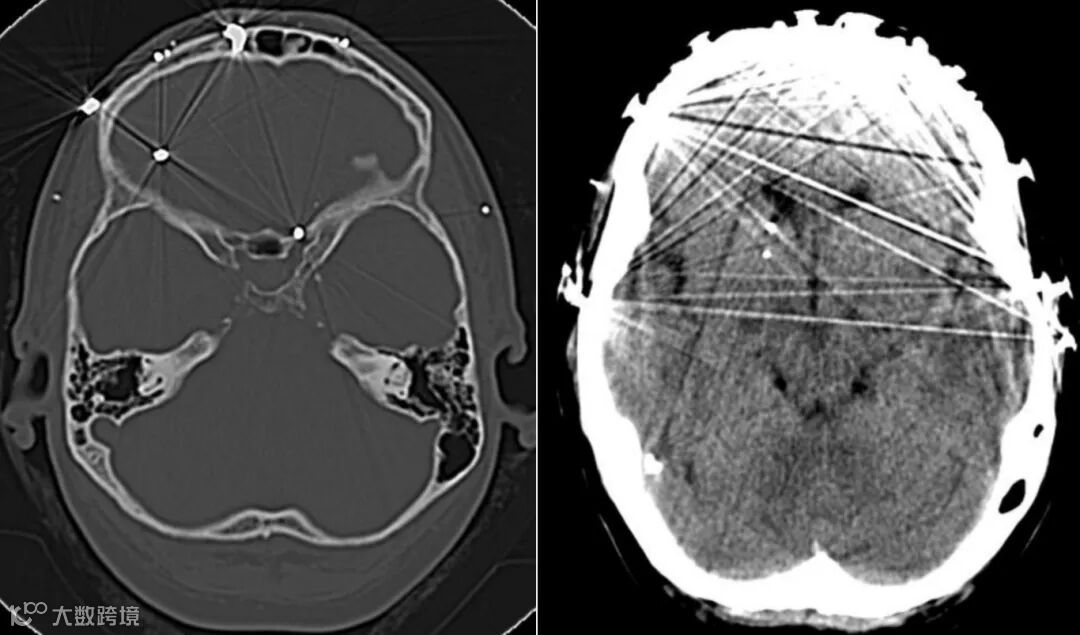

女,40岁,几年前面部曾遭猎枪击中,之后昏迷了5个月,近期头痛加剧。头颅CT示霰弹枪子弹主要位于脑表层。一些子弹穿透了颅骨,位于左额叶、左视神经管附近和右尾状头部。

男,77岁,复发性头痛。33年前头部曾遭受非致命性枪击。CT见穿过两个半球的弹道轨迹、神经胶质增生和多个子弹碎片。